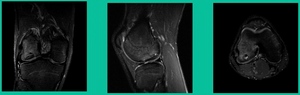

The only other thing to know is about stability. This is probably the most important physiology tenet. This is a biologic problem, because it’s a fracture non-union. But it’s a biomechanical problem because they’ve got a pebble in their shoe when they become symptomatic. So, we talk about the MRIs showing stability. The reality is if they hurt, they probably have microscopic instability. The challenge is if you take a microscopic versus a macroscopically unstable one, the treatment will differ.

This is an 11-year-old. Left knee lateral knee pain. Effusions, the same type of classic findings (Figure 3)

You look at this one, you say, “what are you going to see when you get in there?” This is one when you get in there, you say, I’m not even sure I’m in the right knee because you almost don’t see it. That happens in patients who were painful, but they don’t look macroscopically unstable. Pediatric orthopedic surgeons tend to drill these. These are the ones that I see as failures. I think when you’re talking about something that’s mechanically unstable, it’s hard to understand why drilling would actually make it work without fixation. Even if it’s microscopically unstable.

Another case example. 14-year-old male tennis player, 10 months of knee pain (Figure 7A).

This is a Trochlear defect (Figure 7B).